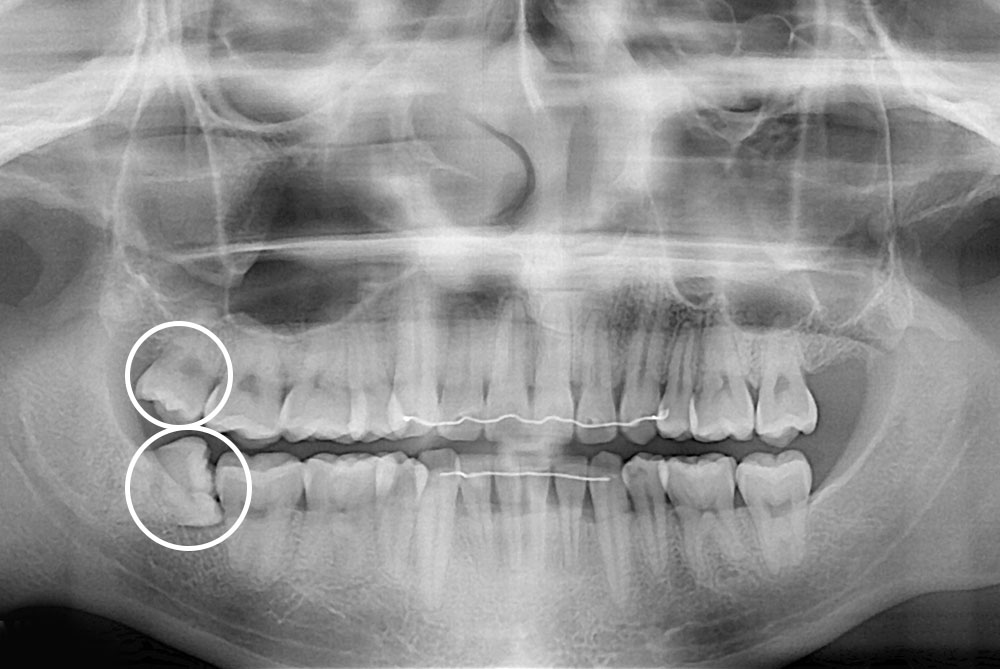

[사랑니] 매복 사랑니 발치

치료후 : 2020-07-04